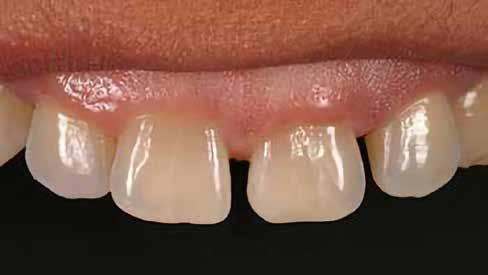

Egy teljes mosoly megtervezésekor vagy javításakor – akár közvetlenül, akár közvetve – a klinikus vagy a technikus alkotó, akinek feladata egy művészi remekmű létrehozása. Egy metszőfogtörés esetében azonban a klinikus kevésbé alkotó, mint inkább kovácsmester, akinek a környező és szomszédos fogazat minden optikai szempontját le kell utánoznia. Ez kihívást jelenthet az árnyalatválasztás szempontjából, mivel a legnagyobb színvariabilitás jellemzően a metszőfogak metsző harmadában található. Ez különösen igaz a fiatalabb páciensekre, akiknek gyakran van kiemelkedő áttetszőségük és opacitásuk ebben a régióban.

Több taktika is segíthet az összetett tömegek rétegződésének kezelésében ezekben a forgatókönyvekben. A palatális stent használata ennek egyik kiszámítható módja (1–4. ábra). Ennél a technikánál a törött területről egy modellen wax-up vagy mock-up készül, és egy gyurma PVS stentet vagy indexet állítanak elő. Ebből egy vékony réteg erős, félig áttetsző kompozit – tipikusan nano- vagy mikrohibrid – kerül a stentre, amely a szájpadlásfelületet reprodukálja. Ezt követően különböző opacitású és transzlucenciájú kompozitrétegeket rétegeznek az arcfelületre, így létrehozva egy zökkenőmentes restaurációt (1. a–c. ábra). Mivel viaszfelvételből készül, az okkluzális tényezőknek jól ellenőrizhetőnek kell lenniük. Ennek a technikának az a hátránya, hogy szükség van egy mock-upra, akár intraorálisan, akár egy modellen történő wax-up segítségével. Ez időigényes lehet, és második időpontot igényelhet, amely nehéz vagy nem praktikus, különösen gyermek- vagy sürgősségi páciensek esetében. Ezenkívül kis törések esetén a kompozittömegek behelyezése nehezebben megoldható, mint nagyobb törések esetén. Egy alternatív megközelítés az „üres vászon technika”, amely gyorsított polikromatikus helyreállítást biztosíthat kisebb törések, sürgősségi esetek vagy gyermekpáciensek esetében. Ez egy kromatikus mikrohibrid alapot használ, amelyet szükség esetén tinták vagy opakok követnek, és egy vékony réteg akromatikus mikrokitöltésű kompozit fed. A cél a törés elfedése és egy élethű, a környező fogazat transzlucenciájának és opacitásának megfelelő helyreállítás biztosítása.

Egy páciens elégedetlen volt a 8. fog incisofaciális felszínén lévő kéthetes restaurációval, mert úgy gondolta, hogy a központi metszőfogak nem illeszkednek egymáshoz. A vizsgálat során megállapították, hogy bár az egyszínű kompozit valóban megegyezett a fog alapszínével, további színre (árnyalatra) volt szükség a szomszédos fog utánzásához (4. ábra).

A fogakat nehéz latexmentes gumidámmal (Isodam, 4D Rubber) izolálták. A meglévő kompozitot eltávolítottuk; egy kromatikus mikrotöltésű kompozitot helyeztünk fel, és egy fehér színt (Creating Color, Cosmedent) vittünk fel egy #8-as K-résszel, vízszintes mozgással, hogy a vízszintes mintázatot lemásoljuk (5. ábra), ezután egy akromatikus mikrotöltésű kompozitot adtak hozzá. A 6. ábra az azonnali posztoperatív eredményt mutatja, a 7. ábra pedig a négyéves utóvizsgálatot, amely a mikrotöltött kompozit megmaradt fényét mutatja.